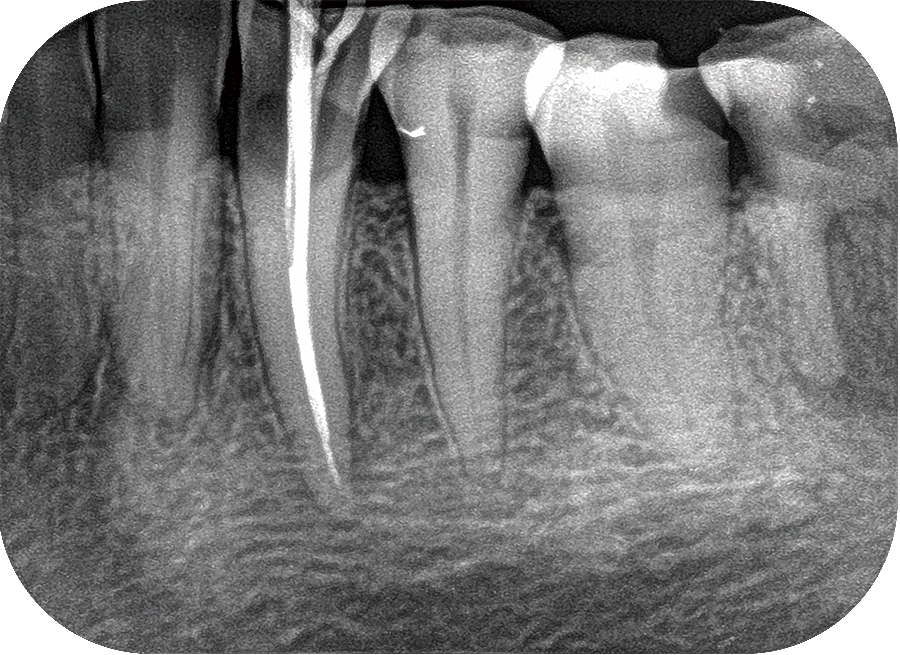

Tujuan dari studi ini adalah untuk membagi gigi menjadi 3 komponen, yaitu email, dentin, dan pulpa. Oleh karena itu, algoritma yang dimodifikasi ini didahului oleh pra-pemrosesan gambar X-ray gigi dan dilanjutkan dengan menggabungkan masing-masing kelompok komponen gigi menjadi satu gambar komposit. Gambar gigi di pra-proses menggunakan Contrast Limited Adequate Histogram Equalization (CLAHE) dan penyesuaian gamma untuk meningkatkan kualitas gambar sinar-X gigi dari pencahayaan yang tidak merata.

Tata ruang bersyarat berbasis kernel Gausian Fuzzy C-Means (GK-csFCM) membagi citra gigi menjadi empat kelompok kelas, yaitu enamel, dentin, pulpa, dan background. Melalui iterasi, pusat-pusat cluster yang dihasilkan lebih konvergen dengan pusat-pusat cluster nyata, sehingga memastikan metode yang diusulkan meningkatkan kelemahan dari metode berbasis FCM yang melekat dan lebih lanjut mempromosikan kinerja segmentasi gambar.

Hasil percobaan pada gambar rontgen gigi nyata menunjukkan bahwa GK-csFCM memiliki kinerja yang lebih baik daripada algoritma klaster FCM dan csFCM dalam hal metrik kualitatif dan kuantitatif, yaitu akurasi, spesifisitas, sensitivitas, dan presisi.